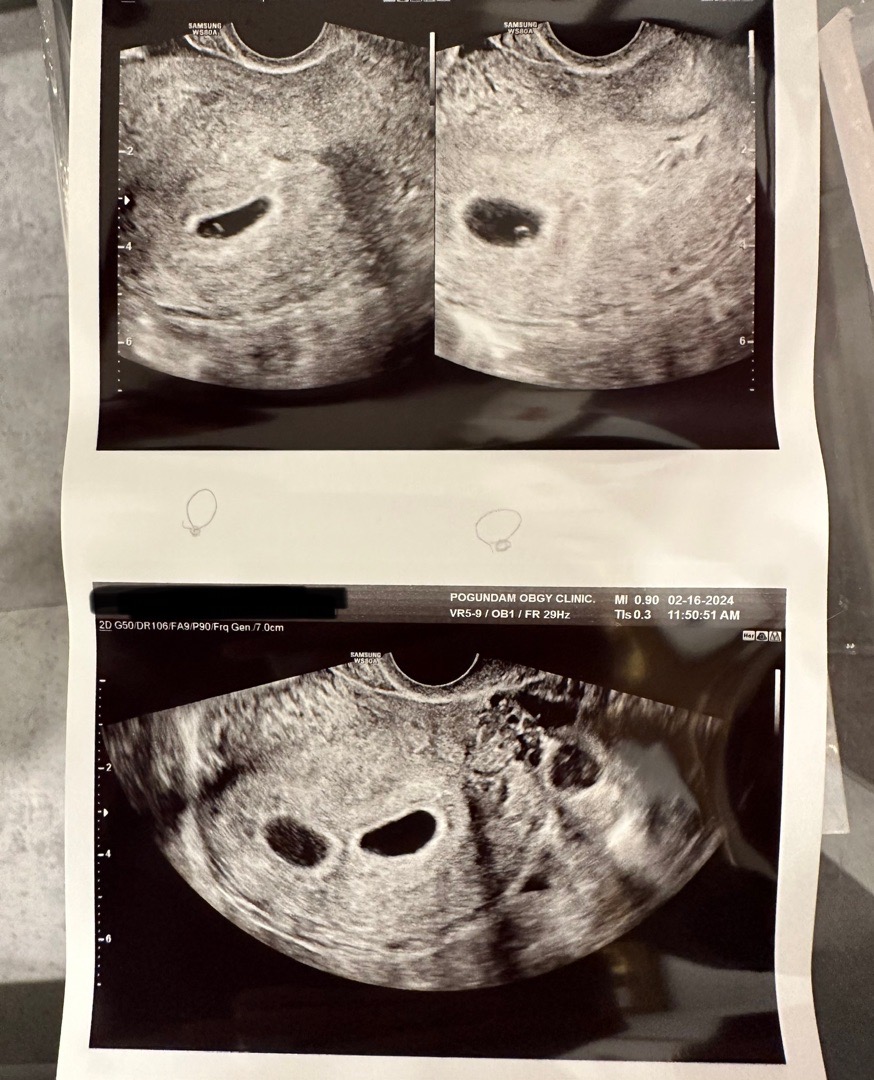

하나가 아니라 둘이었어요..!!

분명 저번주에 하나였는데 ^^^^ 하나가 더 생겼어요… 어떻게 이럴 수가 …????^.ㅜ 축복이지만 걱정도 앞섭니다 ㅠㅠ